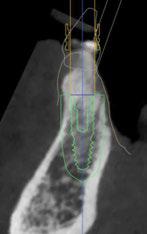

A tenor del estado oral proponemos múltiples opciones terapéuticas, consensuando entre paciente y facultativos una rehabilitación implantoprotésica fija superior e inferior. Debido a la lejanía de la residencia de la paciente, y motivados por las necesidades estéticas que esta exige, consideramos realizar una carga inmediata impresa con resina definitiva el mismo día de la cirugía. Tras el escaneado intraoral con el escáner Dexis IS3700 (Figuras 7 y 8) y realización de CBCT, subimos los ficheros a la plataforma Bego Guide,

procediendo a realizar una solicitud de encargo a través de un formulario. Antes de 72 horas recibimos una propuesta terapéutica. En ella se facilitan vistas 3D detalladas, así como valoraciones y consideraciones a tener en cuenta durante el fresado y la inserción de los implantes (Figuras 9 a 19). Decidimos realizar extracción de todas las piezas remanentes, dada su nula viabilidad a corto-medio plazo y en Bego (a través del portal) proponen mantener 3 piezas (las más viables técnicamente) en cada arcada para proporcionar el anclaje óptimo de la

Figura 9. Propuesta de planificación maxilar con encerado diagnóstico digital. Se visualiza emergencia de los implantes y emergencia protésica con pilares angulados.

Figura 10. Propuesta de planificación maxilar con encerado diagnóstico digital. Destaca la angulación del implante 1.6 esquivando el seno maxilar con un ángulo de inserción de 30 º y una emergencia protésica verticalizada.

Figura 12. Encerado diagnóstico digital teniendo en consideración un aumento de la dimensión vertical.

Figura 13. Representación gráfica de la futura colocación de los implantes y su relación con la rehabilitación.

16. Superposición radiológica implante 45 angulado, teniendo en consideración el encerado diagnóstico y preservando estructuras nerviosas.

Figura 14. Representación tridimensional. Destaca la protección de estructuras nobles (nervio mentoniano) al presentar un implante angulado con íntima relación.

Figura 15. Visión general tridimensional. Destaca la uniformidad en la disposición de los implantes. En amarillo emergencia implantológica y en gris emergencia protésica mediante pilares transepiteliales angulados multiplus.